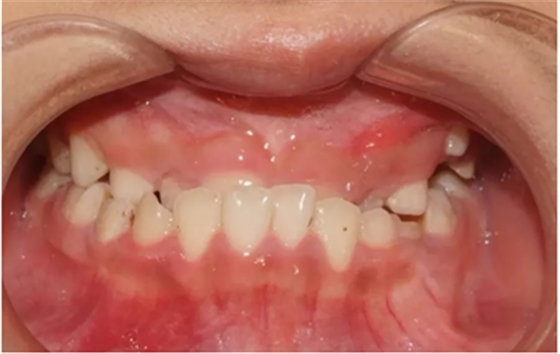

01 反頜

反頜通常被稱為“地包天”,也有些是個別牙反頜。該如何避免?